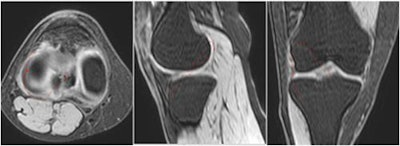

Aiming to assess the viability of determining graft length using 3D-printed knee models instead, Pavan and colleagues collected T1-weighted images of the knee of 16 volunteers acquired with a 1.5-tesla MRI machine (Achieva 2.6, Philips Healthcare). There were six female and 10 male participants; their average age was 27, and they all had healthy ACLs.

Next, the researchers used several open-source, image-processing software (Osirix; Meshmixer; Cura; Slic3r) to segment and edit the MRI scans and finally create a 3D virtual model. After smoothing the virtual model and converting the file into stereolithography (STL) format, they 3D printed it with a 3D printer (Ultimaker 2+, Ultimaker) and polylactic acid material.

An orthopedic surgeon measured the transepicondylar femoral axis and calculated the graft length on the resulting 3D-printed models using a plastic cable as a graft simulator. A separate orthopedic surgeon and radiologist performed the same measurements on corresponding multiplanar reconstruction MRI scans.